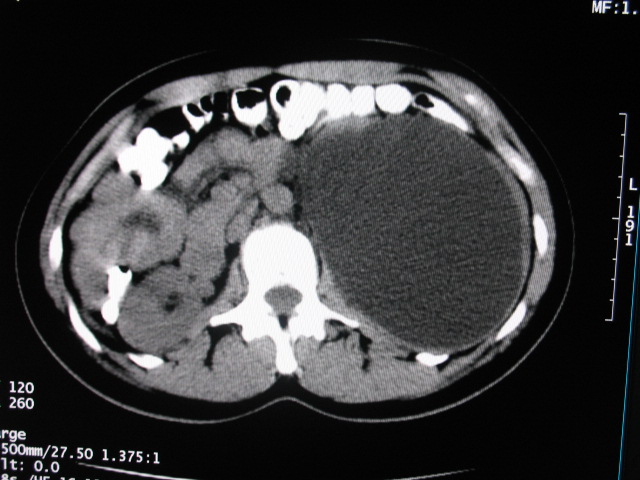

女,28岁,自觉腹部包块一年余

考虑左侧双肾盂双输尿管畸形,其中一输尿管末端梗阻(不排除异位开口可能)并相应之肾盂及输尿管明显扩张积水。

考虑左侧双肾盂双输尿管畸形,其中一输尿管末端梗阻并输尿管肠管样扩张盂曲、肾盂囊状扩张积水。

考虑左侧双肾盂双输尿管畸形,其中一输尿管末端梗阻(不排除异位开口可能,不知病人有无不自觉溢尿,有可能开口于阴道或宫颈,也可下端为盲端)并相应之肾盂及输尿管明显扩张积水。

术后证实是左侧双肾盂双输尿管畸形,巨输尿管巨肾盂症